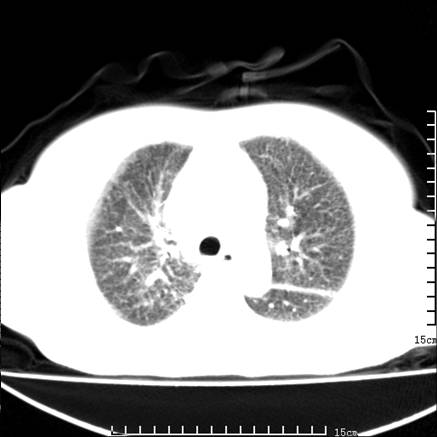

女,王某,58岁,咳嗽三个月余,基层医院二个月前诊为肺结核,用抗结核药二个月无明显疗效。

心包积液致肺瘀血.右侧周围型肺癌伴肺内转移,中间裂积液,叶间胸膜肥厚.右上肺大泡,右侧胸膜肥厚.

双肺继发型tb,心功能不全并肺淤血、心包、双侧叶间裂积液,肺大泡,右下胸膜肥厚钙化。

支持  双肺继发型tb,心功能不全并肺淤血、心包、双侧叶间裂积液,肺大泡,右下胸膜肥厚钙化。